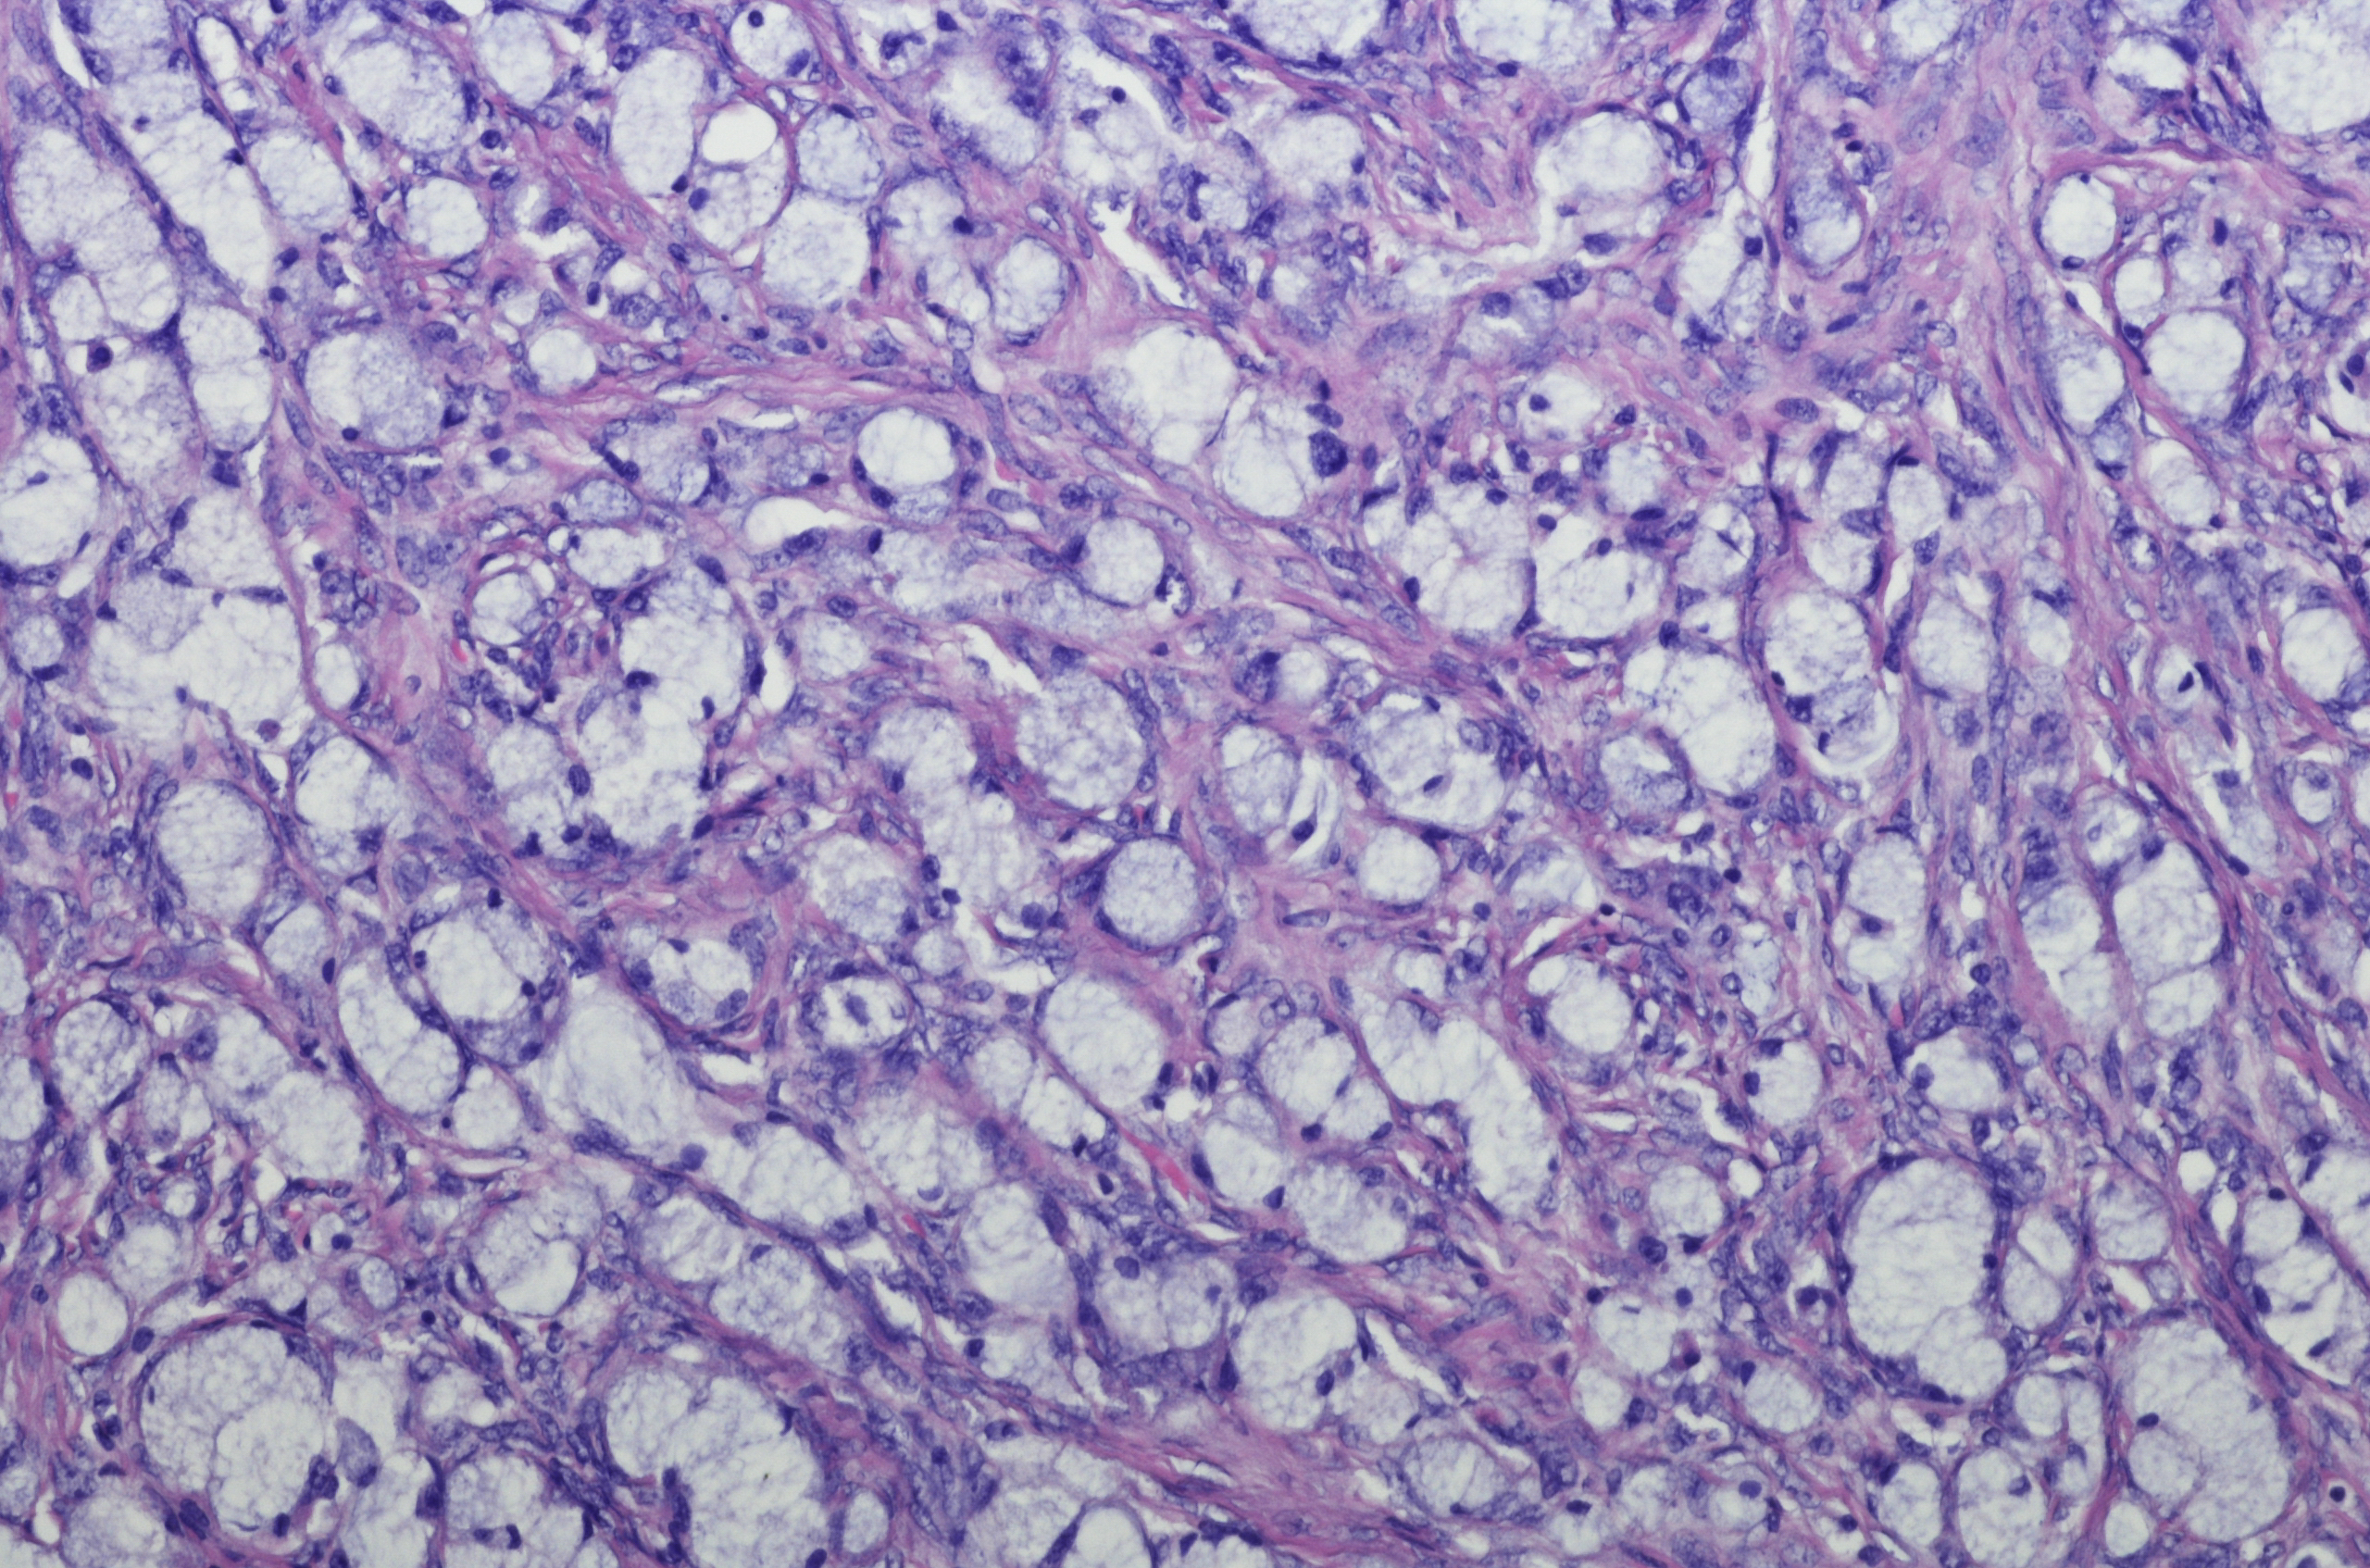

• Kidney health true true

Kidney health

Improving global kidney health by understanding kidney disease

Our work identifies and understands the incidence, prevalence and history of kidney disease at a population level so we can find solutions and treatments.

In collaboration with Royal Prince Alfred Hospital, we aim to identify and understand the incidence, prevalence and history of kidney disease at a population level. Through this work, we seek to find solutions and treatments for kidney disease including: